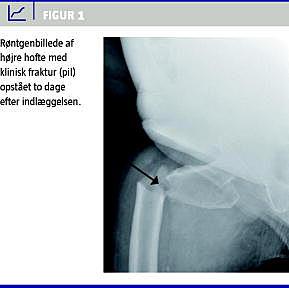

To dage efter indlæggelsen faldt patienten ved forflytning mellem stol og seng. En akut røntgenundersøgelse viste herefter en disloceret, subtrokantær, højresidig hoftefraktur (Figur 1 ). Frakturen blev efterfølgende osteosynteret med glideskrue og marvsøm.